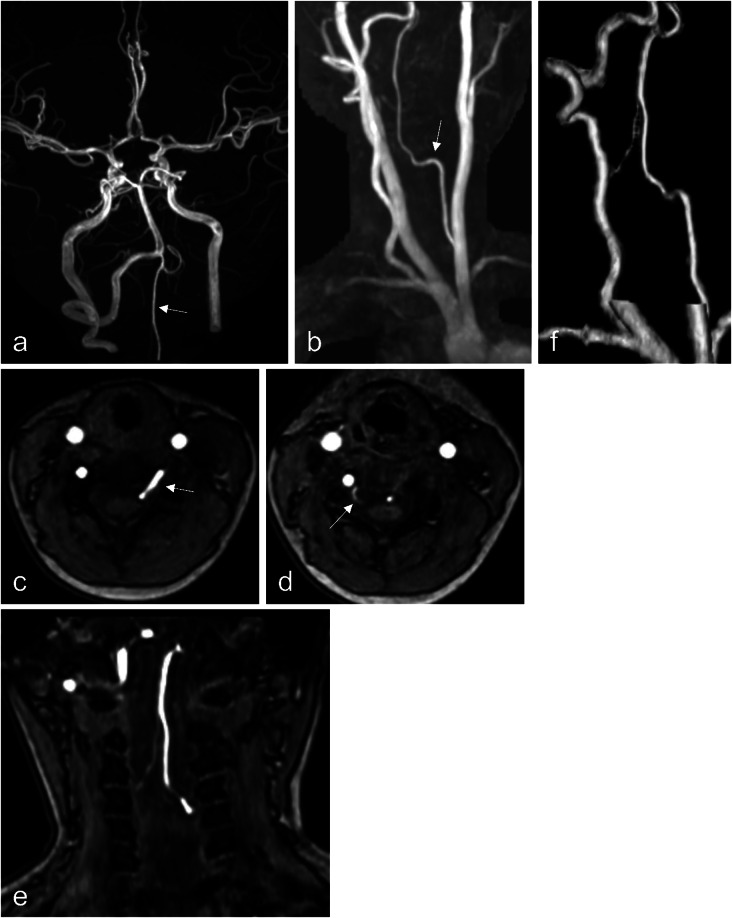

Purpose: The vertebral artery (VA) typically enters the subarachnoid space at the atlanto-occipital region. However, segmental variations can occur, with the VA entering the spinal canal at atypical levels. While a C3 segmental VA has been reported, no prior studies describe a C5 segmental VA. This case represents the first documented occurrence of this anomaly.

Methods: An 8-year-old girl underwent brain magnetic resonance imaging for headache screening, which incidentally revealed an abnormal VA course.

Results: Imaging revealed the absence of the left VA at the proximal V2 segment. Instead, a radiculomedullary artery at C4/5 entered the spinal canal and contributed to the formation of the anterior spinal artery (ASA), which ascended along the spinal cord. The right VA appeared normal; however, a radiculomedullary artery at the C3/4 level was identified, joining the contralateral radiculomedullary artery at the C1 level to form the ASA. Additionally, bilateral accessory middle cerebral arteries were observed. No clear association was found between this anomaly and the patient's headache, and she remained under observation.

Conclusion: This anomaly may result from persistence of the fifth intersegmental artery. The vascular course resembled collateral circulation observed in acquired VA occlusion. Given its proximity to the spinal cord, potential risks include ischemic complications and spinal cord compression. This case highlights the importance of accurate imaging and careful surgical planning. Further studies on these rare vascular anomalies will enhance our understanding of VA variations and their clinical significance.